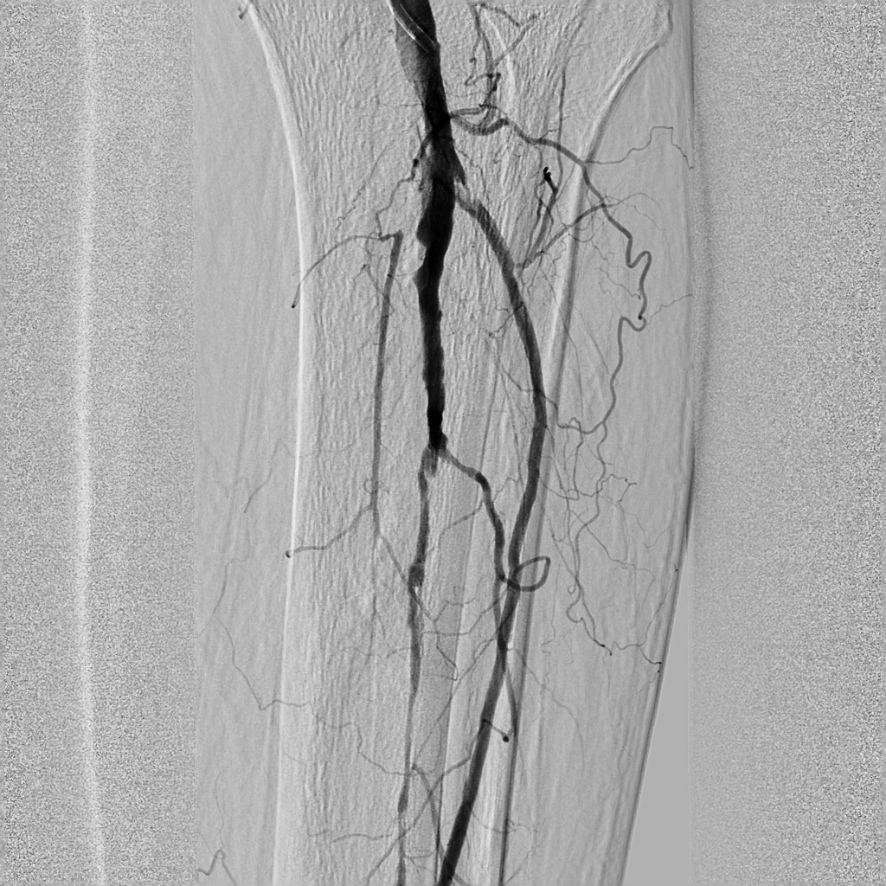

Ангиография при тромбозе нижних конечностей: медицинские исследования